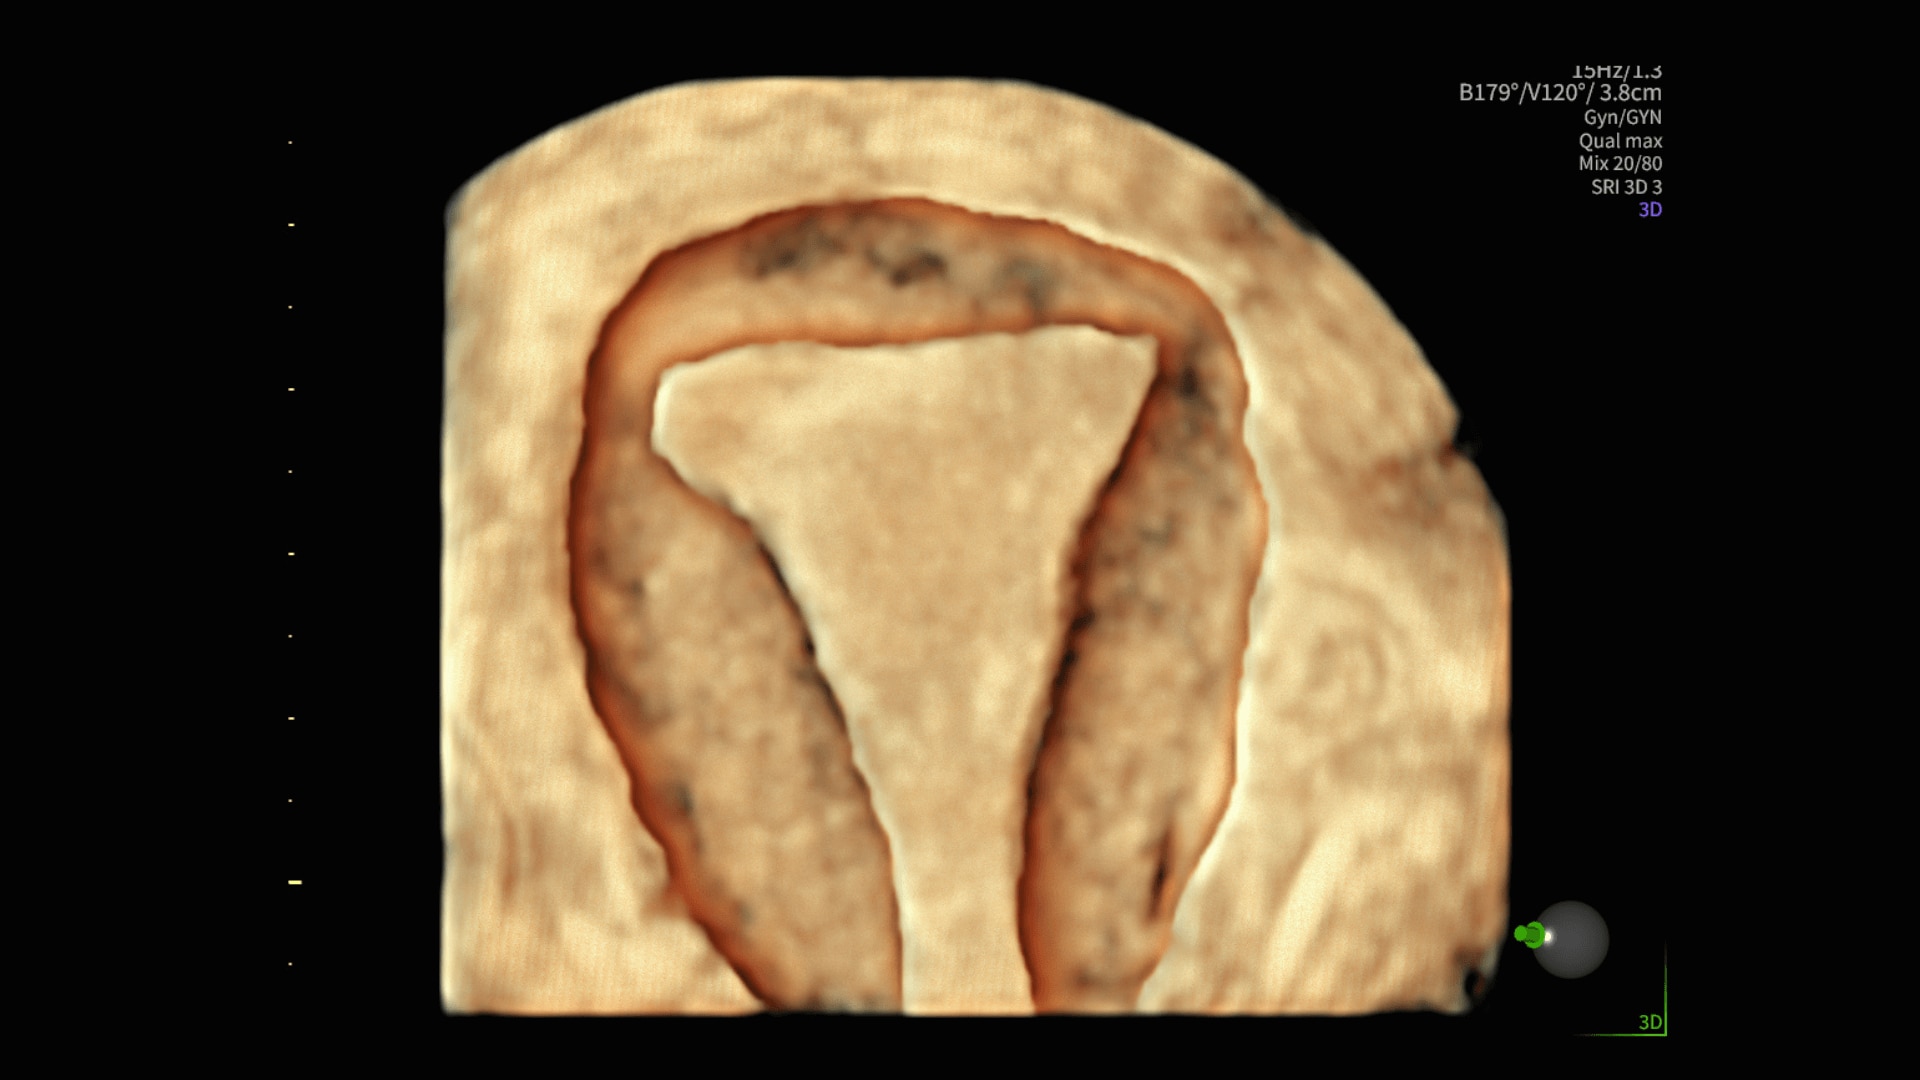

Segment fibroids with 88% accuracy using Fibroid Mapping

50%

Shadow Reduction

Confident answers

Shadow Reduction decreases shadows on B-mode imaging that can obscure adjacent structures, helping restore tissue information and borders.